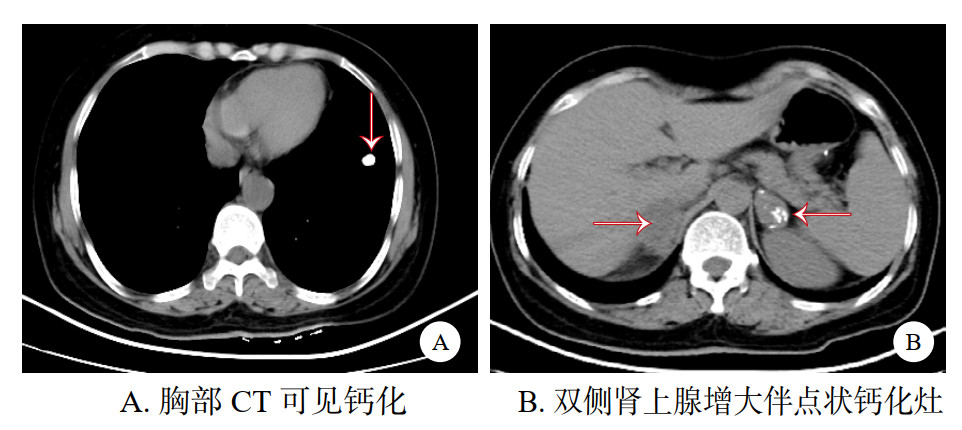

1 资料与方法患者女性,58岁,因“反复恶心1月余加重伴头晕胸闷一天”于2024-03-02入院。1月前患者开始出现反复恶心,并伴有食欲减退,恶心呕吐症状逐渐加重,期间在当地卫生院就诊,服用抑酸护胃类药物,症状未见明显改善。2024-03-02 19:00左右患者感头晕、胸闷不适,肢体乏力症状较前明显加重,家属遂送至本院急诊。查体BP: 90/40 mmHg (1 mmHg=0.133 kPa)、HR: 108次/min、R: 18次/min、昏睡状态,呼之能应,肤色黝黑。急诊血气分析pH: 7.37、PCO2: 32.8 mmHg、PO2: 277 mmHg(FiO2 41%)、血电解质Na+ 125 mmol/L、K+: 4.4 mmol/L HCO3-: 18.8 mmol/L, BE -5.4 mmol/L, Lac: 1.4 mmol/L, Hb: 15.4 g/dL、血糖6.2 mmol/L。头胸及全腹部CT显示: 双侧基底节腔隙梗塞,两肺纹理增多、两上肺钙化灶,双侧肾上腺占位伴钙化、胆囊结石、左肾小结石,(见图 1)。心电图: ①窦性心动过速;②异常Q波(Ⅱ、Ⅲ、aⅤF);③ST-T改变(Ⅱ、Ⅲ、aⅤF、Ⅴ4、Ⅴ5、Ⅴ6);④ 肢导联低电压。急诊予以鼻塞吸氧、补液、升压、护胃止吐、纠正电解质紊乱等对症治疗,考虑患者病情危重,以“休克”收入本院EICU。入院后追问患者家人,患者近2年来逐渐出现乏力,全身皮肤逐渐变黑,由头面部开始,逐渐过渡至手足各关节,胃纳差,消瘦,未予重视,体重下降14 kg。

| 图 1 胸腹部CT |

本文报道的病例发生误诊误治分析原因如下:①发病隐匿:该患者两年来逐渐出现肢体乏力伴皮肤色素沉着,体重缓慢下降,未予重视,最终以恶心呕吐为首发症状并出现意识障碍伴血压下降才入院治疗。整体病程长,发病早期无明显阳性体征,患者本身易忽视,急诊医师问诊时同样容易遗漏。②由于低热和消化道症状,一线医师诊断为脓毒性休克,出现误诊误治。AC临床表现有两种状态,其一、表现为恶心呕吐、腹痛、谵妄、低钠血症、高钾血症、低血糖、发热、休克等,可伴有白细胞增高,但不合并感染,如本例情况,多见于肾上腺皮质功能明显低下者。其二、AI患者合并感染诱发AC发生,此时鉴别诊断较为困难,除AC的表现外,还合并有感染的征象,此时对于感染相关的依据应该积极寻找,可按脓毒性休克指南规范进行,同时积极寻找感染灶,其中PCT、乳酸、凝血功能、病原学检查如血培养、mNGS等。两者治疗的共同点均要及时补充适量糖皮质激素。该患者危象入院后查PCT及白细胞均在正常范围内,无感染症状,近期亦无其他应激事件发生,发生无明显诱因可循。但近1个月恶心呕吐症状进行性加重,形成恶性循环,最终导致肾上腺危象。在给予糖皮质激素后临床表现逐渐改善,循环逐渐恢复正常。该患者考虑AC后,未第一时间使用激素治疗,在第2日早八点留取血皮质醇及促肾上腺皮质激素标本后使用氢化可的松治疗,病情2 h左右改善。同时患者T-spot结果阳性,CT提示两上肺钙化灶(见图 1),双侧肾上腺占位伴钙化。由于无肺结核感染症状,故考虑原发性肾上腺结核可能,建议为明确病因可行肾上腺穿刺活检,同时经验性行抗结核治疗,但患者无盗汗、低热等感染症状,患者本人及家属拒绝活检及抗结核治疗,最终未能明确诊断。